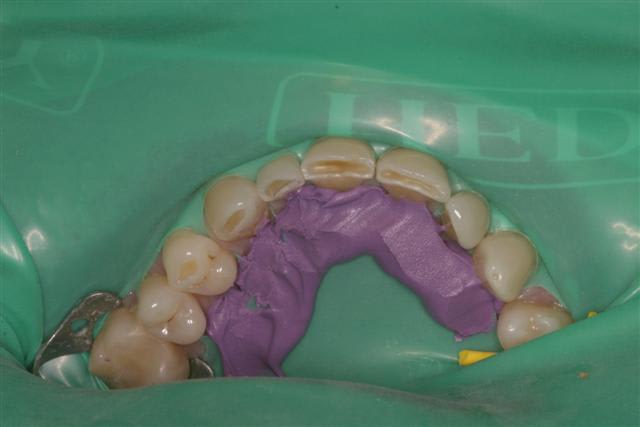

Même et surtout pour les cas complexes (essai et cimentation de 6 à 10 unités céramique)la digue est un outil très utile. Je peux etcher, placer l'adhésif, prendre mon temps pour coller sans avoir la langue, la salive etc.